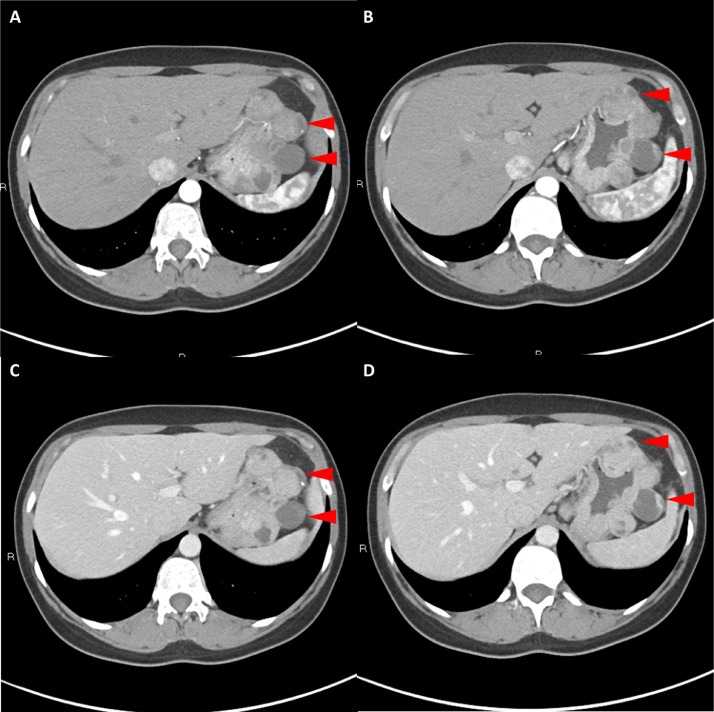

Fig. 4

圖 4: 胃腸道間質瘤的三維表示。 (A 和 B)胃腸道間質瘤在動脈期和冠狀面的 3D 可視化提供了進一步的解剖細節(jié)和空間信息。